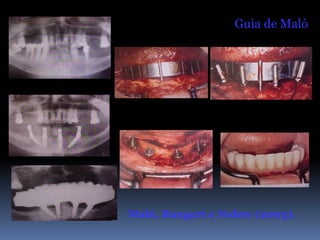

Guia de Maló

Maló, Rangert e Nobre (2003).